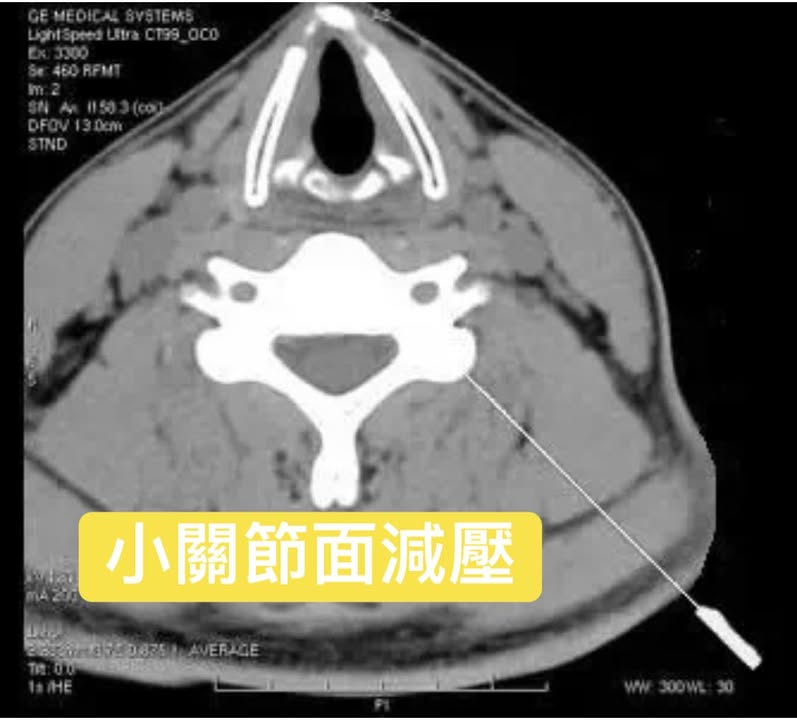

患者去台大神經外科找某資深主治權威醫師,原本是要詢問一個骨頭良性囊腫問題,後來聊到十幾年的左側腰痛(當年做完椎間盤切除術後的後遺症),患者笑著說來接受中醫微創針刀療法,效果出乎意料的好,沒想到該權威也認同這種軟組織鬆解的減壓術,一聽到我們結合MRI/RAY/CT/ECHO四種定位,也覺得這個方法很不錯,囑咐患者持續來診治療。